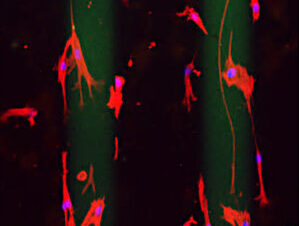

En el marco de este estudio los investigadores observaron que regiones peri-tumorales del microambiente tumoral se caracterizan por ser áreas de gran rigidez, creando caminos preferenciales para que las células tumorales se desplacen e inicien metástasis en órganos distales.

Los investigadores observaron que las regiones peri-tumorales del microambiente tumoral tienen gran rigidez, lo que crea caminos preferenciales para el desarrollo de la metástasis

Así, para demostrar que este fenómeno ocurre en organismos vivos y no solo en experimentos de laboratorio in vitro, el equipo empleó ratones modificados genéticamente y un fármaco experimental, JP-153 cuyo mecanismo de acción bloquea de manera específica un mecano-sensor expresado en células tumorales, formado por la unión de las proteínas FAK y paxilina. El resultado fue contundente: inhibir la durotaxis tumoral redujo de manera significativa del número de metástasis desde el páncreas hacia el hígado.